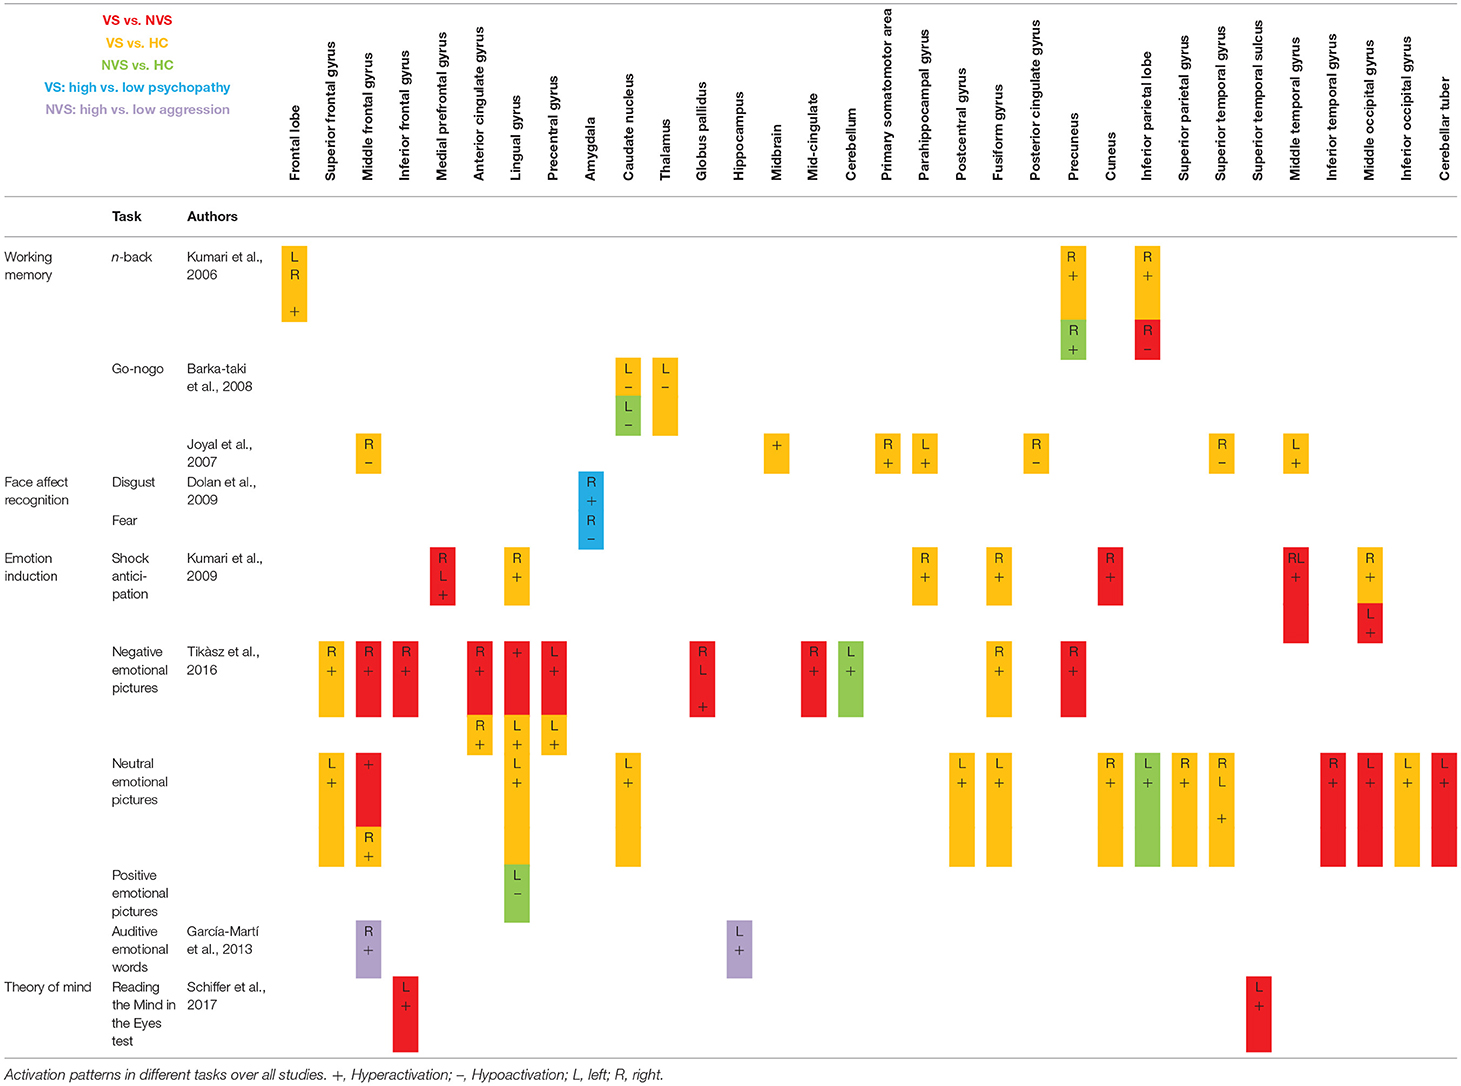

Activation Patterns

Table 2 shows fMRI activation patterns across all tasks, brain areas, and group comparisons. For readers interested in more detail in the individual studies, the following sections summarize their results and provide tables about the specific areas and tasks involved. Bearing in mind Table 2, readers can choose to jump directly to the discussion section.

Working Memory

When operationalizing working memory functioning with Go/No-Go, VS vs. HC hypoactivated the right middle frontal gyrus, right posterior cingulate gyrus, and right superior temporal gyrus (31). In contrast, VS as opposed to HC hyperactivated the left middle temporal gyrus, midbrain, right primary somatomotor area, left parahippocampal gyrus (31) and hypoactivated the left thalamus and left caudate nucleus (26). NVS as opposed to HC hypoactivated solely the left caudate nucleus.

Working memory as measured by the n-back task showed that VS vs. HC hyperactivated the frontal lobe bilaterally, the right precuneus, and the right inferior parietal lobe. NVS vs. HC hyperactivated the right precuneus, while VS vs. NVS hypoactivated the right inferior parietal lobe (27). Table 3 shows an overview.

Synthesis of Findings From Studies Using Working Memory Paradigms

In Figure 2, we provide an overview on working memory activation patterns over all reviewed studies. As shown in Figure 2A, violent as opposed to non-violent persons with schizophrenia showed hypoactivation in the right inferior parietal lobe. This is an area known for being part of the working memory network, but it has until now not been observed in specific aggression paradigms. The hypoactivation seen in this group comparison may therefore not be specific for aggression, but may represent working memory dysfunction in the VS group.

Figure 2. Working memory activations. Overview of the working memory brain activation patterns reported by the reviewed studies. Hyperactivations are shown in red, hypoactivations in blue. (A) shows the activation patterns in the group comparison VS vs. NVS with VS<NVS in blue (shown slice numbers are 210, 220, 230, 240) in the contrast 2-back vs. 0-back, (B) shows the activation patterns in the group comparison VS vs. HC with VS>HC in red (shown slice numbers are 170, 180, 190, 200) in the contrasts 1- and 2-back vs. 0-back and cognitive (go/no-go task) vs. reference condition and VS<HC in blue (shown slice numbers are 160, 170, 180, 190) in the contrast NoGo20 vs. NoGo40 and NoGo40 vs. Go and cognitive (go/no-go task) vs. reference condition, (C) shows the activation patterns in the group comparison NVS vs. HC with NVS>HC in red (shown slice numbers are 170, 180, 190, 200) in the contrast 1- and 2-back vs. 0-back.

Figure 2B shows hyperactivations of VS as compared to HC mainly in the frontal lobe and in the middle temporal gyrus. In addition, we see hypoactivations of VS as opposed to HC in the right middle frontal gyrus, the cingulate gyrus, and in the superior temporal gyrus. As frontal regions are typically involved in working memory tasks, this finding is in line with the literature.

In Figure 2C, we present the activation patterns of NVS as compared to HC. NVS hyperactivate the left caudate nucleus and precuneus. The precuneus is known to be involved in working memory processes, while the caudate nucleus usually is not. Still, the latter—as a feedback processor—might be under higher workload conditions while solving these tasks in persons with schizophrenia than in healthy controls. Also, this could be an indicator toward the hypothesis that schizophrenia patients solve working memory tasks differently, namely trying to use information from past experiences to influence their decisions in the tasks.